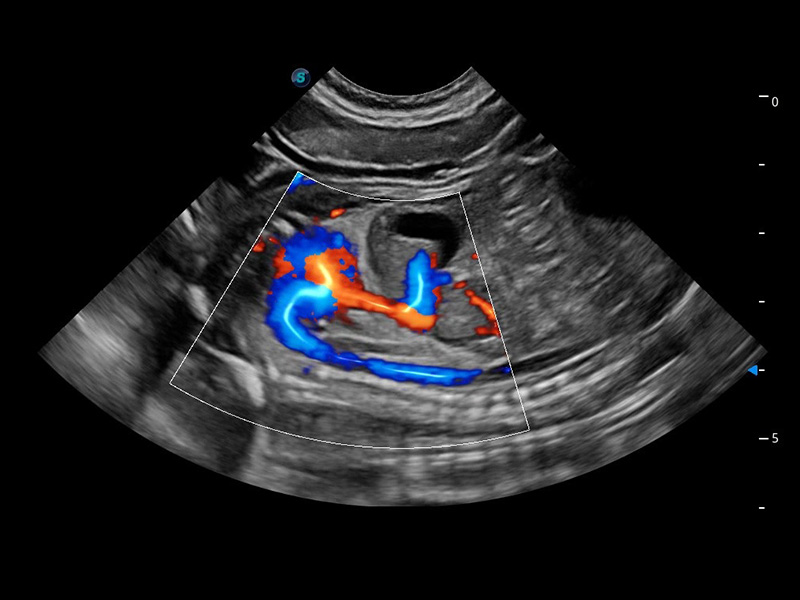

ProPet 60 作為一款高端臺(tái)式動(dòng)物超聲設(shè)備,為動(dòng)物醫(yī)生的日常診斷提供了一系列貼合動(dòng)物臨床需求、解決臨床實(shí)際問(wèn)題的高級(jí)成像功能。憑借全系列高清探頭,滿(mǎn)足醫(yī)生對(duì)腹部、心臟、生殖、淺表、肌骨等成像的所有需求,切實(shí)幫助您提升檢查效率,提高診斷信心。